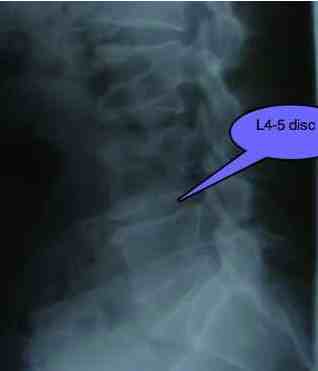

• Separately, both obesity (because it changes your posture, increasing the lumbar lordosis as pregnancy does) and poor muscle tone greatly increase the chance of slipped disk. Interesting Australian medical research found a direct correlation between the number of hours of TV watched and disease in general. More heart disease, more back pain... L4 Low back pain disease ...